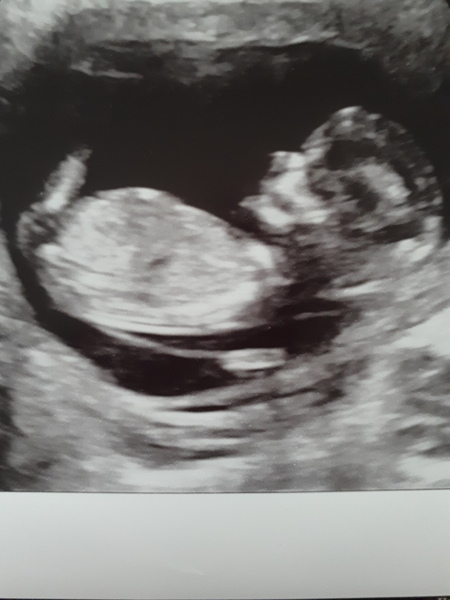

I checked in early But have been lurking since. Had my scan this week. It's a pain already... would not hold still and kept hiding but all fine. Had the screening never occurred to me to ask the internet what it all means. MN to the rescue. Thanks @lookatthemoon for the link! Mind at rest now. Fly out on holiday on sunday... will be able to enjoy it a bit more now! And just to share the goodness, I'll attempt to attach a pic.

BlackCat what a lovely scan photo :)

BlackCat what a lovely scan photo!

And, because why not, pic attached.

Great scan pictures blackcat and llama!!